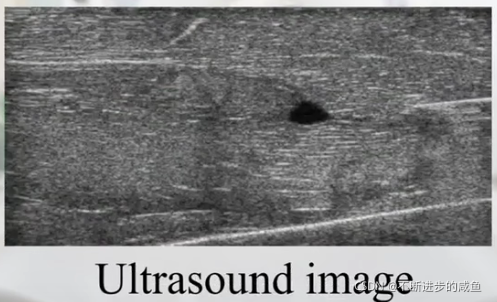

(8)超声图像:

(4)超声图像: 超声图像很难看懂,因为图像视野狭窄,图像精度也不好,但是绿色对人体无害。